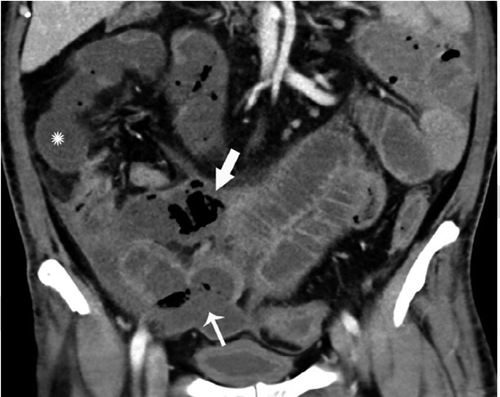

В частности, как пояснил специалист, у некоторых пациентов с COVID-19 внезапно развивался пневматоз - патологическое состояние системы пищеварения, при котором газы проникают в толщу стенки кишечника и образуют там воздушные кисты. Кроме того, у нескольких людей было выявлено необычное желтое обесцвечивание кишечника, еще у трех больных - инфаркт кишечника.

© Radiology